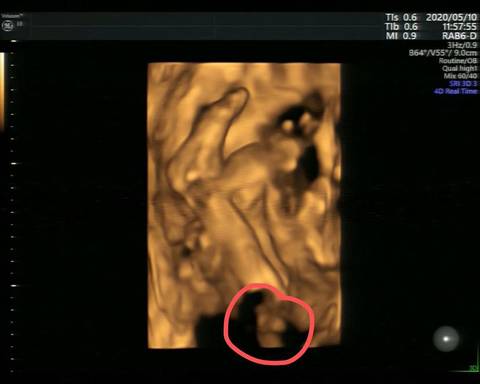

摘要:通過四維彩超技術(shù),我們能夠清晰地觀察到胎兒蛋蛋的形態(tài),揭示早期胎兒發(fā)育的神秘面紗。這一技術(shù)能夠展示胎兒在母體內(nèi)的成長過程,幫助我們更深入地了解胎兒的發(fā)育狀況。通過這一探索,我們能夠獲取關(guān)于胎兒健康的重要信息,為母嬰健康提供有力支持。

在四維彩超下,胎兒蛋蛋呈現(xiàn)出一定的形態(tài),通常情況下,胎兒蛋蛋呈現(xiàn)橢圓形,表面光滑,隨著胎兒的發(fā)育,蛋蛋會逐漸增大,在觀察過程中,醫(yī)生還會關(guān)注蛋蛋的位置和與周圍組織的關(guān)系,以確保胎兒發(fā)育正常。

需要注意的是,由于胎兒的生長發(fā)育是一個復(fù)雜的過程,四維彩超下的胎兒蛋蛋形態(tài)可能因個體差異而異,在觀察胎兒蛋蛋時,醫(yī)生會結(jié)合具體情況進(jìn)行分析,以確保診斷的準(zhǔn)確性。